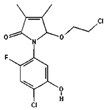

| Compound Name | Pubchem ID | Molecular Formula | Molecular Weight (g/mol) | Drug Likeliness | Bioavailability Score | BBB Permeant | Structure |

|---|---|---|---|---|---|---|---|

| Stigmasterol | 5280794 | C29H48O | 412.7 | 0.62 | 0.55 | No |  |

| Quercetin | 5280343 | C15H10O7 | 302.23 | 0.52 | 0.55 | No |  |

| Kaempferol | 5280863 | C15H10O6 | 286.24 | 0.50 | 0.55 | No |  |

| beta-Sitosterol- beta-D-glucoside | 12309055 | C35H60O6 | 576.8 | 0.5 | 0.55 | No |  |

| beta-Sitosterol | 222284 | C29H50O | 414.7 | 0.78 | 0.55 | No |  |

| Racemosol | 624971 | C21H24O4 | 340.4 | 0.36 | 0.55 | Yes |  |